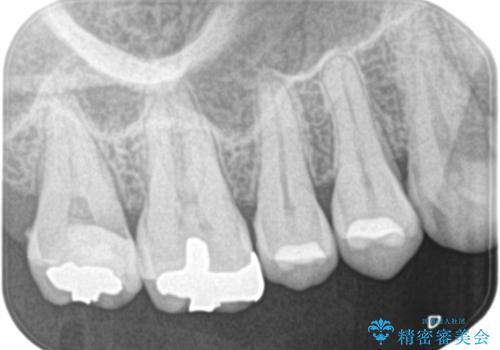

- 左上の奥歯がズキズキ痛い、冷たいものも長引く痛みがあると来院されました。

根管治療を行った後にオールセラミッククラウンにて修復しております。

根管治療を行った場合、破折リスクを軽減するために被せ物を行っております。